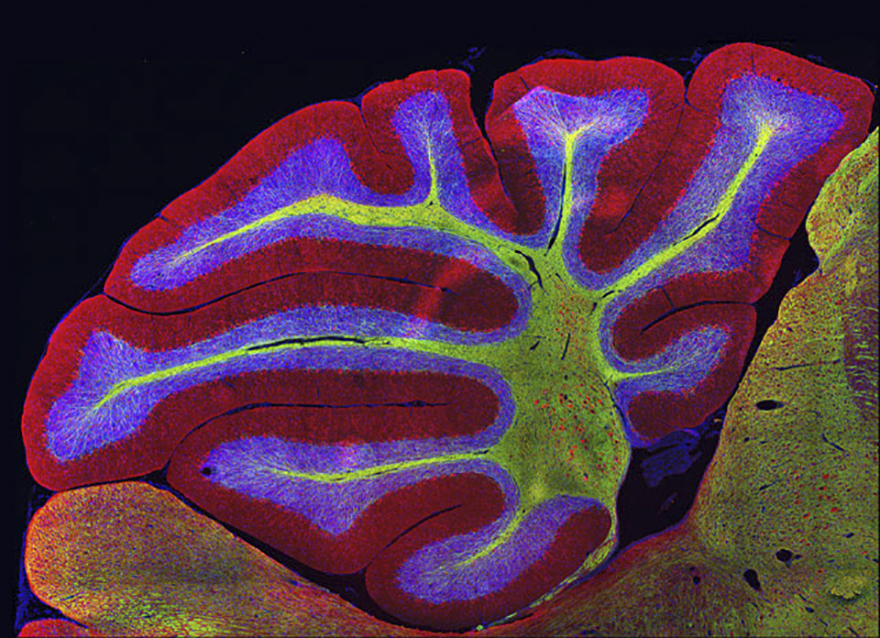

Sagittal Section Of Mouse Cerebellum (Brain), Athens, Image Of Distinction